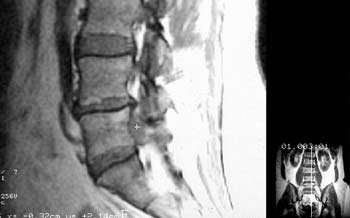

Рис 1. Большая секвестрированная грыжа диска L5-S1. (Слева) Сагитальный скан до контрастирования. (Справа) Аксиальный скан после введения магневиста.